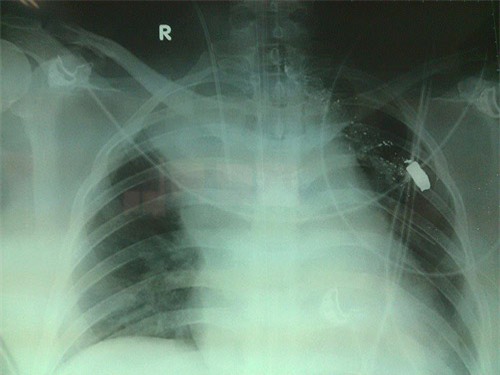

Theo ghi nhận của phóng viên tại khoa Hồi sức Tích cực (Bệnh viện Việt Đức), bệnh nhân hiện tại vẫn đang trong tình trạng bất tỉnh, thở máy và viên đạn vẫn chưa được lấy ra.

Theo các bác sĩ khoa Hồi sức tích cực, bệnh nhân nhập viện Việt Đức trong tình trạng có vết thương ở nền cổ và ngực trái do bị đạn bắn. Bệnh nhân mới được mổ lấy thai nhi ở bệnh viện tuyến dưới.

Ngay sau khi tiếp nhận bệnh nhân, các bác sĩ Bệnh viện Việt Đức đã nhanh chóng tiến hành hồi sức bệnh nhân, hiện tại bệnh nhân đang bị sốc nhiễm trùng nặng, phải nằm thở máy cố định một chỗ nên chưa thể phẫu thuật lấy viên đạn ra được.

Ngoài sốc nhiễm trùng, bệnh nhân còn bị tổn thương phổi nặng, phải điều trị nhằm bảo vệ phổi. Đồng thời, các bác sĩ đang nghi ngờ vết thương của bệnh nhân ảnh hưởng đến dây thần kinh. Bởi, hiện tại hai chân của bệnh nhân không thể cử động được.